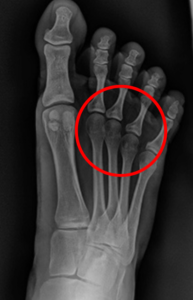

Prueba de rayos X: ¿Mejoran la alineación de los dedos?

El análisis de rayos X es una de las pruebas más reveladoras, ya que permite observar el impacto estructural de los separadores de dedos en el pie. Estos aparatos realmente consiguen una separación de los dedos aumentando el espacio entre ellos. Ahora bien, podríamos pensar que esa separación también se produce en el espacio entre las cabezas metatarsales.

Al hacer las radiografías con los separadores puestos observamos que mientras se separan los dedos, se produce un efecto cizalla y se aproximan los metatarsianos. Es decir, a nivel metatarsal generan un efecto parecido a llevar un calzado que nos comprimiese. Es importante resaltar que entre las cabezas metatarsales discurre el paquete vascular y nervioso que va a cada uno de los pies. Generar una disminución de ese espacio puede agravar ciertas patologías como el Neuroma de Morton.

Radiografía de paciente con separador de dedos

Bajo nuestro criterio, no tiene sentido que, si el objetivo de los separadores de dedos es que el pie se expanda, coloquemos algo que hace el efecto contrario en los metatarsianos.